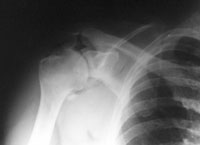

Ein 44-jähriger Patient ist auf dem ersten Eis des Winters ausgerutscht und auf die rechte Schulter gestürzt.

Er klagt über starke Schmerzen im Bereich der rechten Schulter und ein Instabilitätsgefühl im Gelenk. Die Beweglichkeit des Arms ist aufgrund der Schmerzen eingeschränkt, Durchlutung und Sensibilität sind normal.